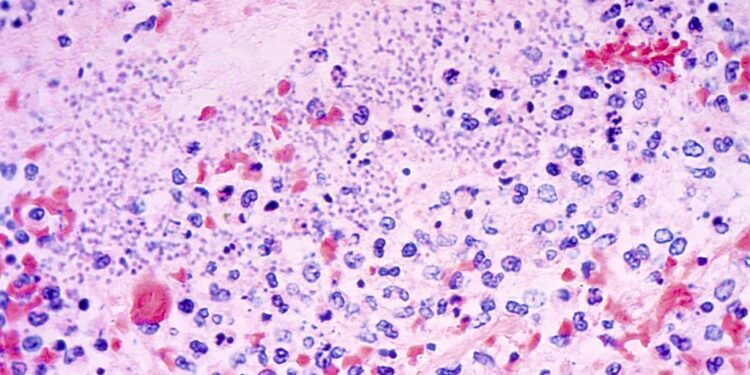

Pneumonic plague, which happens when the bacterium Yersinia pestis will get into an individual’s lungs, is each “the least frequent and most harmful sort of plague,” in response to the Cleveland Clinic.